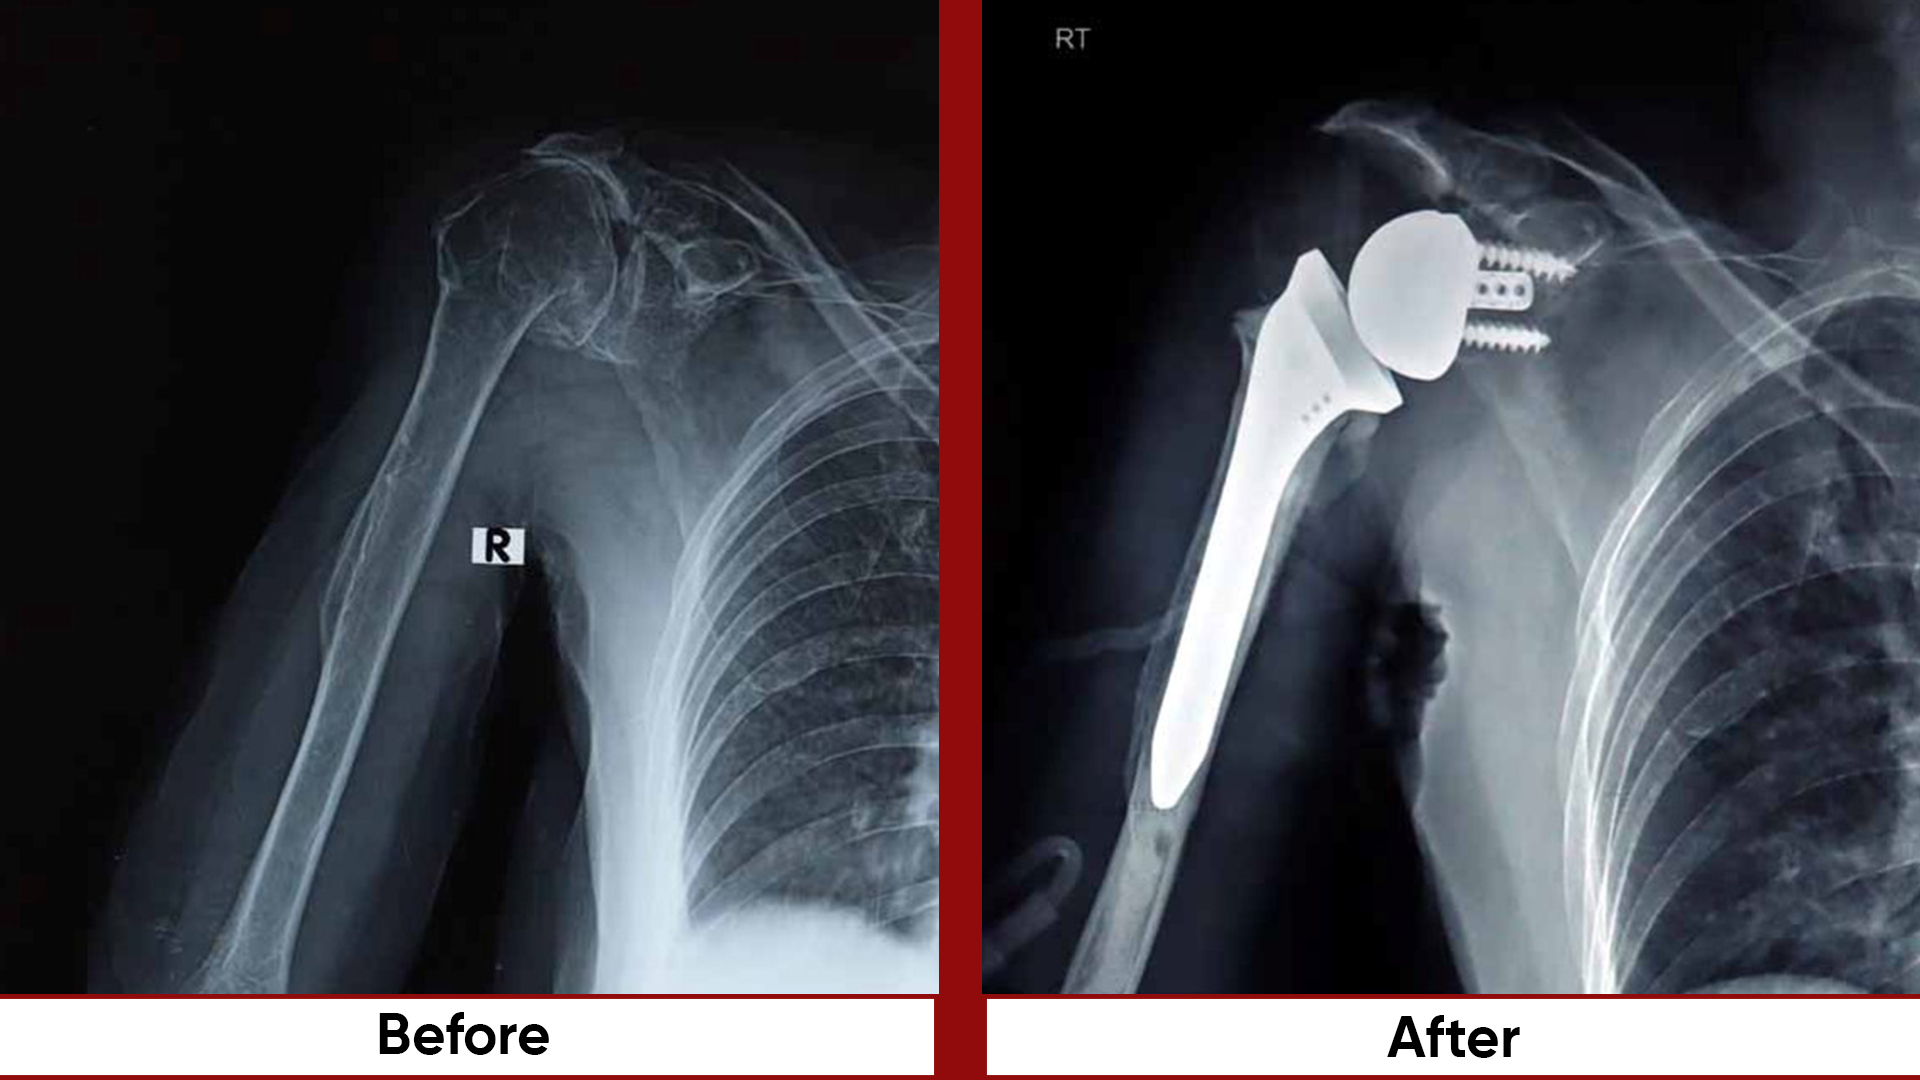

Procedures

• Arthroscopic Surgeries (Knee & Shoulder)

• Joint Preservation Surgery